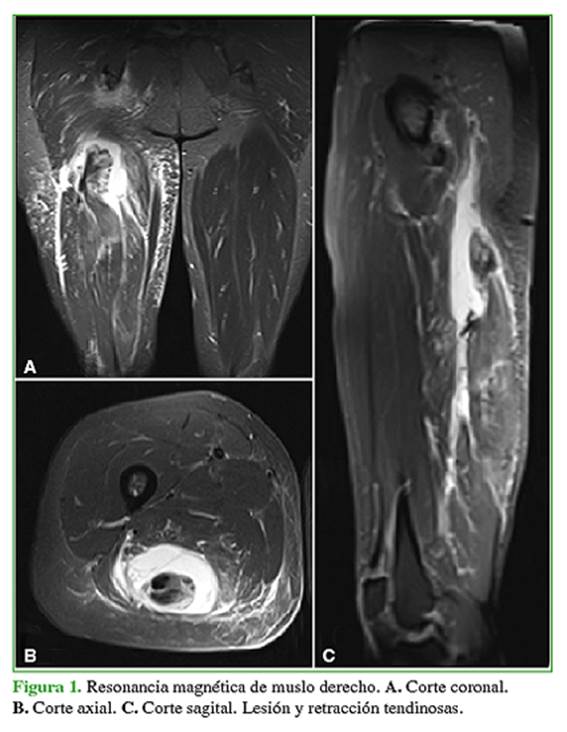

Mujer de 43 años, sin antecedentes patológicos, maratonista, que sufre una caída desde su propia altura con el miembro inferior derecho en extensión de rodilla y flexión de cadera. Consulta por dolor posterior de muslo con irradiación a la pierna que se exacerba al extender la rodilla. Se realiza una ecografía musculoesquelética que muestra una rotura completa de la unión miotendinosa proximal del semimembranoso y desgarro total del tendón conjunto. La RM de muslo derecho muestra una retracción tendinosa hacia caudal de aproximadamente 6 cm (Figura 1). Se decide el tratamiento quirúrgico.